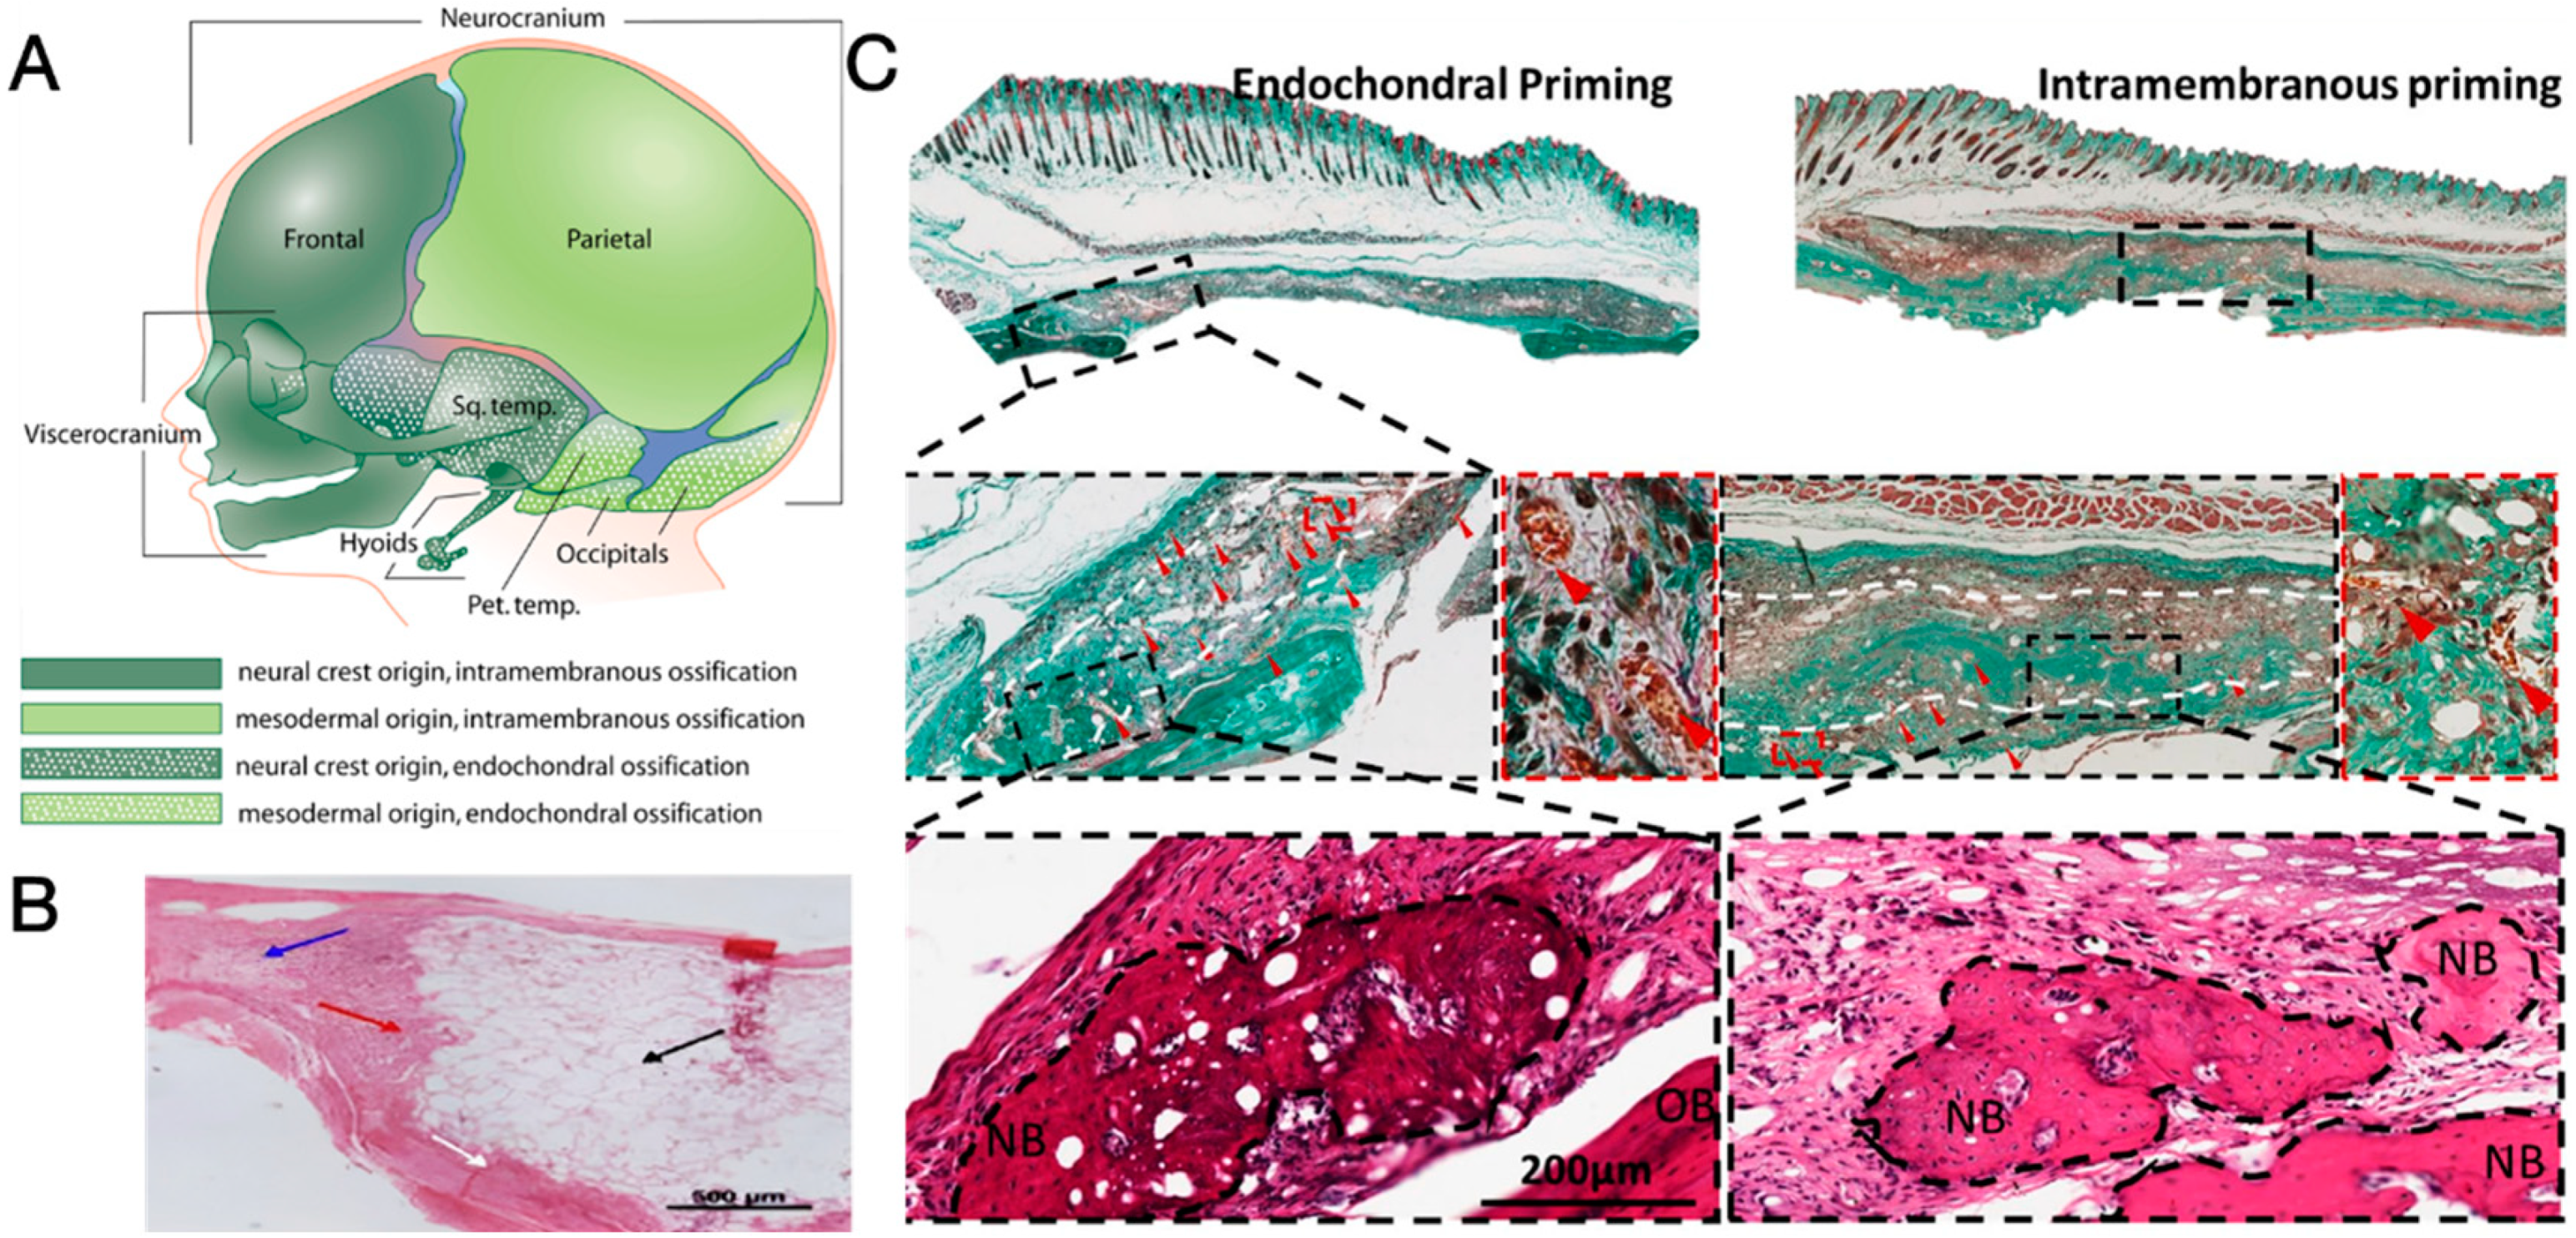

2. Regeneration Capacity of Cranium

2.1. Biological Basis of Cranium Regeneration

- Wang, D.; Gilbert, J.R.; Zhang, X.; Zhao, B.; Ker, D.F.E.; Cooper, G.M. Calvarial Versus Long Bone: Implications for Tailoring Skeletal Tissue Engineering. Tissue Eng. Part B Rev. 2020, 26, 46–63. [Google Scholar] [CrossRef] [PubMed]

- Percival, C.J.; Richtsmeier, J.T. Angiogenesis and intramembranous osteogenesis. Dev. Dyn. 2013, 242, 909–922. [Google Scholar] [CrossRef] [PubMed]

- Ko, F.C.; Sumner, D.R. How faithfully does intramembranous bone regeneration recapitulate embryonic skeletal development? Dev. Dyn. 2021, 250, 377–392. [Google Scholar] [CrossRef] [PubMed]

- Galea, G.L.; Zein, M.R.; Allen, S.; Francis-West, P. Making and shaping endochondral and intramembranous bones. Dev. Dyn. 2021, 250, 414–449. [Google Scholar] [CrossRef] [PubMed]